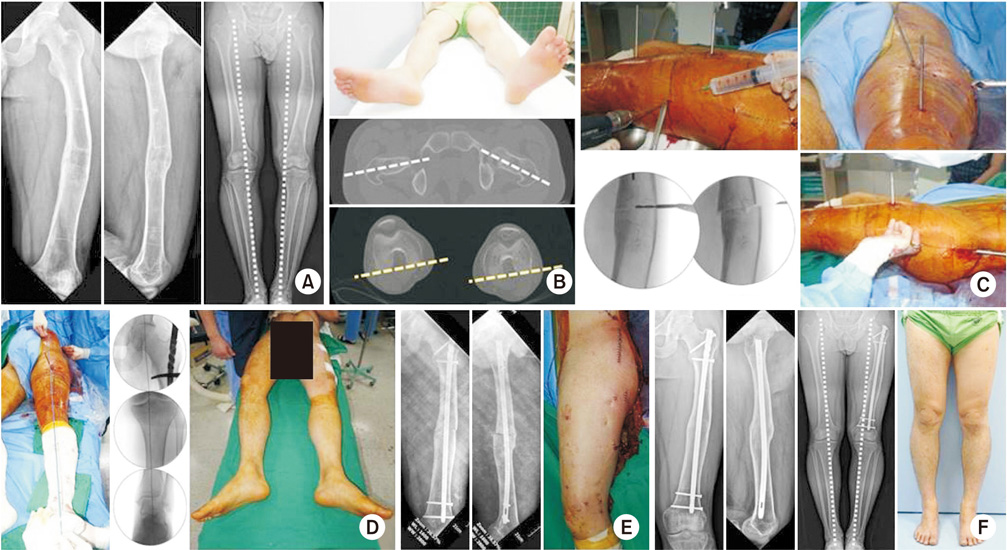

(A) A 23-year-old man presented varus deformity after conservative treatment from a left femoral fracture at childhood. Mechanical axis was slightly shifted to the medial side compared with the right side. (B) Physical examination showed that the position of the left foot was rotated inward, and a computed tomography scan confirmed an increased femoral internal rotation. (C) The metal pin was inserted parallel to the anterior femur and then percutaneously osteotomized. After that, the pins fixed in parallel were rotated to correct the desired degree of rotational alignment, and intramedullary nail was inserted. (D) After the correction, the mechanical axis was passed to the center of the knee and the operation was completed. The position of the foot was similar on both sides. (E) On postoperative radiographs, it was confirmed that varus deformity was corrected, and the osteotomy site showed minimal incision. (F) One year later, osteotomy was well united, angulation and rotational deformity were corrected, and the mechanical axis was restored.

jkfs-30-219-g007.jpg

Fig. 7 (A) A 23-year-old man presented varus deformity after conservative treatment from a left femoral fracture at childhood. Mechanical axis was slightly shifted to the medial side compared with the right side. (B) Physical examination showed that the position of the left foot was rotated inward, and a computed tomography scan confirmed an increased femoral internal rotation. (C) The metal pin was inserted parallel to the anterior femur and then percutaneously osteotomized. After that, the pins fixed in parallel were rotated to correct the desired degree of rotational alignment, and intramedullary nail was inserted. (D) After the correction, the mechanical axis was passed to the center of the knee and the operation was completed. The position of the foot was similar on both sides. (E) On postoperative radiographs, it was confirmed that varus deformity was corrected, and the osteotomy site showed minimal incision. (F) One year later, osteotomy was well united, angulation and rotational deformity were corrected, and the mechanical axis was restored.